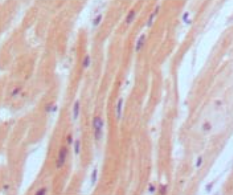

IHC    1/200 - 1/1000